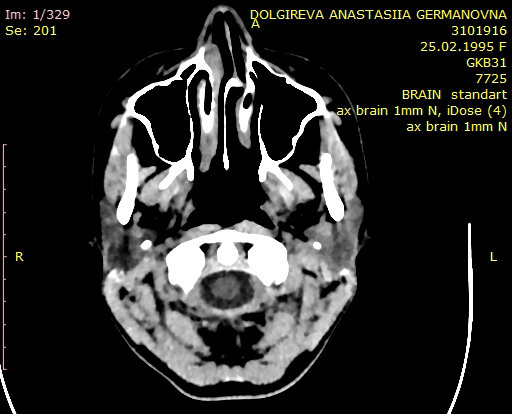

25 февраля 1995 года появилась на свет девочка, но свет она так и не увидела. Девочку звали Настя и она — тотально незрячая с самого рождения.

Причиной потери зрения стала неосторожность врачей. Настю уронили в родильном доме и, с тех пор, её жизнь проходит в абсолютной темноте. У неё нет никаких зрительных ощущений, и даже в воображении — темно. Главными источниками информации о мире для Насти стали слух, осязание, обоняние, и другие органы чувств.